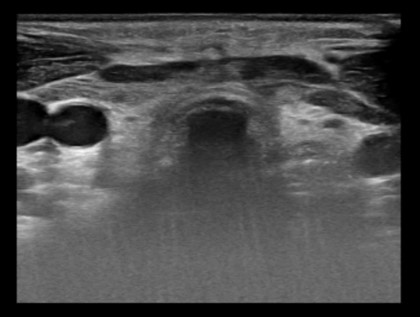

– Siêu âm tuyến giáp:

Hình ảnh nhân hai thùy tuyến giáp – TIRADS 3 / Bướu giáp Basedow.